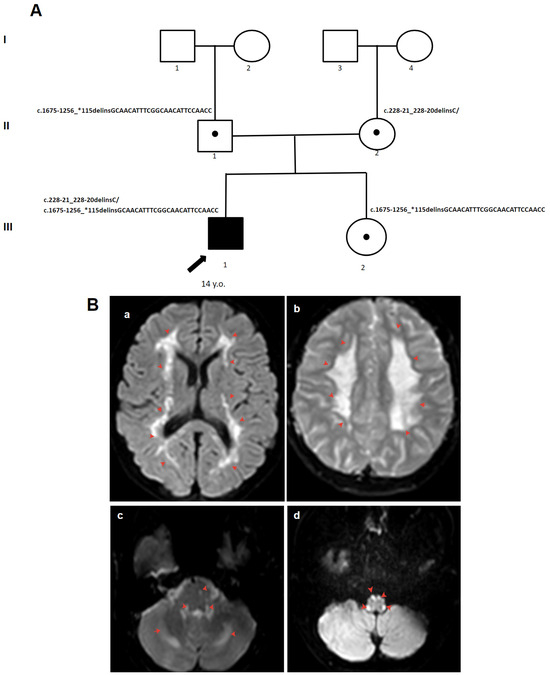

3.1.2. Patient 2